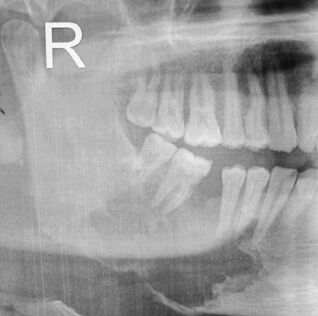

(B)在X光片檢查時,放射線骨壞死區域都呈現骨頭被蠶食(moth-eaten bone)的外觀

moth-eaten影像: SqCC,osteosarcoma,osteomylitis

orn影像:

課本沒有特別的形容詞,個人覺得比較適合的敘述是看得出原本的型態但聚集在一起的multiple RL